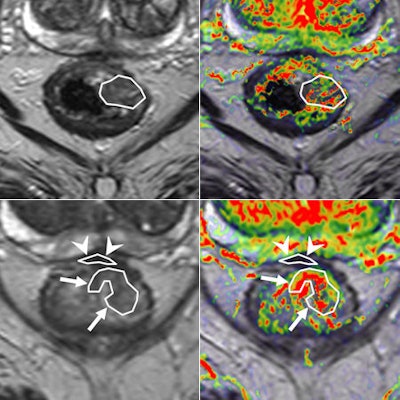

Perfusion MRI of a rectal tumor compared with histology. Top left: T2-weighted MR image of a patient with rectal tumor (encircled) before chemoradiotherapy. Top right: Corresponding perfusion MR image (K-trans map). There is a heterogeneity in tumor angiogenic activity with areas of higher (red) and lower K-trans values. Bottom left: T2-weighted MR image of the same patient after irradiation of the tumor. Bottom right: Corresponding perfusion MR image (K-trans map). Residual tumor (white arrows) is visualized, showing persistent heterogeneous angiogenic activity with areas of high (red) and low K-trans values (arrowheads pointing at fibrosis in the anterior rectal wall). All images courtesy of Dr. Regina Beets-Tan, PhD.

Perfusion MRI of a rectal tumor compared with histology. Top left: T2-weighted MR image of a patient with rectal tumor (encircled) before chemoradiotherapy. Top right: Corresponding perfusion MR image (K-trans map). There is a heterogeneity in tumor angiogenic activity with areas of higher (red) and lower K-trans values. Bottom left: T2-weighted MR image of the same patient after irradiation of the tumor. Bottom right: Corresponding perfusion MR image (K-trans map). Residual tumor (white arrows) is visualized, showing persistent heterogeneous angiogenic activity with areas of high (red) and low K-trans values (arrowheads pointing at fibrosis in the anterior rectal wall). All images courtesy of Dr. Regina Beets-Tan, PhD.However, she emphasized that before these biomarkers can be used in imaging practice, validation of the techniques is required to confirm whether "what you see is also what you get." Ultimately, in the multicenter setting, protocol standardization and implementation are needed to enable large patient cohort validation.